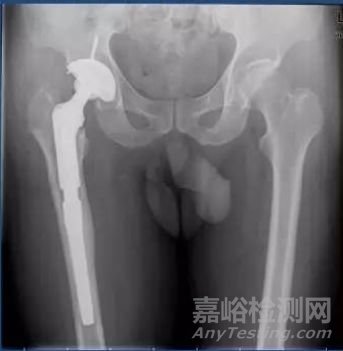

1.2. 按照產(chǎn)品固定方式劃分:某些醫(yī)療器械需要進行相關(guān)固定才可發(fā)揮其作用,因此可按照產(chǎn)品固定方式進行相關(guān)劃分。例如對于人工髖關(guān)節(jié)假體系統(tǒng)而言,因固定方式不同,可劃分為骨水泥型髖關(guān)節(jié)假體和非骨水泥型關(guān)節(jié)假體。從臨床角度出發(fā),之所以這么劃分,是因為這兩種髖關(guān)節(jié)假體工作機理雖然大致一樣,但是其固定方式的不同。而這種固定方式的不同,直接和臨床療效緊密相關(guān)。骨水泥型假體柄在固定時,是在骨水泥泥團樣未固化期時,填入假體和骨的縫隙中,固化后骨水泥起到空間充填鑲嵌作用而固定假體,同時起到載荷應(yīng)力傳遞;而非骨水泥型假體柄在固定時,初始依靠的是機械卡壓力量維持穩(wěn)定,后期固定依靠的是骨長入假體中表面涂層的多孔表面起到固定作用;兩種固定方式的不同,也決定了相關(guān)預(yù)后情況;因此雖然其均是髖關(guān)節(jié)假體系統(tǒng),但是仍需按照不同的注冊單元進行相關(guān)劃分。

髖關(guān)節(jié)假體系統(tǒng)(圖片來源自互聯(lián)網(wǎng))

部分器械,即使是同一注冊單元下的產(chǎn)品,在臨床試驗設(shè)計階段,也可能需要分為不同的臨床試驗單元進行相關(guān)臨床試驗設(shè)計。例如,同樣是一個注冊單元的骨水泥型髖關(guān)節(jié)假體,但是仍需要根據(jù)預(yù)期申報的適用范圍不同(初次置換、假體翻修、腫瘤關(guān)節(jié)置換),劃分為不同的臨床試驗單元進行試驗。從臨床角度出發(fā),其主要原因在于適用范圍不同,其面對的情形完全不同。譬如初次髖關(guān)節(jié)置換和翻修型髖關(guān)節(jié)置換,其手術(shù)難度和創(chuàng)傷程度完全不同。初次髖關(guān)節(jié)假體置換,手術(shù)入路解剖清晰,幾乎不存在骨缺損、假體難以取出等相關(guān)問題;而翻修則面臨著手術(shù)入路解剖不清晰,髖臼側(cè)骨缺損,假體難以取出,大量截骨后肌肉止點無處附著等一系列情形,相關(guān)手術(shù)創(chuàng)傷、手術(shù)時間、出血量及術(shù)后康復(fù)情形完全不同。其次,兩者器械的基本結(jié)構(gòu)和組成也不一樣,因為是根據(jù)不同情形進行的相關(guān)設(shè)計。例如,相對于初次置換的髖關(guān)節(jié)假體而言,翻修型假體往往具有更長的股骨柄和更為靈活放置的髖臼側(cè)假體;而此類器械的區(qū)別也會導(dǎo)致在手術(shù)使用過程中的差異。因此,雖然均是骨水泥型髖關(guān)節(jié)假體系統(tǒng),兩者仍需要進行臨床試驗單元劃分后,再進行相關(guān)臨床試驗。

翻修型髖關(guān)節(jié)假體系統(tǒng)術(shù)后(圖片來源自互聯(lián)網(wǎng))